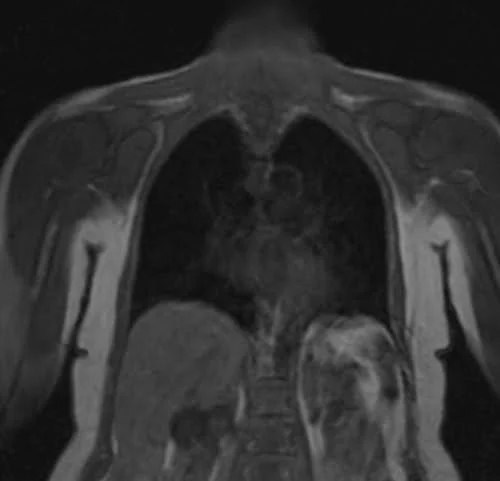

The care bolus image looks similar to the T1 localizer scans, with contrast in the blood vessels appearing bright during image acquisition.

CARE BOLUS SEQUENCE USED IN CHEST ANGIOGRAPHY